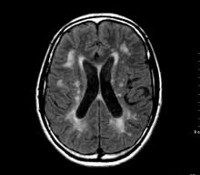

Этиологические факторы ДЭП тем или иным способом приводят к ухудшению мозгового кровообращения, а значит к гипоксии и нарушению трофики клеток головного мозга. В результате происходит гибель мозговых клеток с образованием участков разрежения мозговой ткани (лейкоареоза) или множественных мелких очагов так называемых «немых инфарктов».

Наиболее уязвимыми при хроническом нарушении мозгового кровообращения оказываются белое вещество глубинных отделов головного мозга и подкорковые структуры. Это связано с их расположением на границе вертебро-базилярного и каротидного бассейнов. Хроническая ишемия глубинных отделов мозга приводит к нарушению связей между подкорковыми ганглиями и корой головного мозга, получившему название «феномен разобщения». По современным представлениям именно «феномен разобщения» является главным патогенетическим механизмом развития дисциркуляторной энцефалопатии и обуславливает ее основные клинические симптомы: когнитивные расстройства, нарушения эмоциональной сферы и двигательной функции. Характерно, что дисциркуляторная энцефалопатия в начале своего течения проявляется функциональными нарушениями, которые при корректном лечении могут носить обратимый характер, а затем постепенно формируется стойкий неврологический дефект, зачастую приводящий к инвалидизации больного.

В рамках диагностики дисциркуляторной энцефалопатии проводится консультация офтальмолога с офтальмоскопией и определением полей зрения, ЭЭГ, Эхо-ЭГ и РЭГ. Важное значение в выявлении сосудистых нарушений при ДЭП имеет УЗДГ сосудов головы и шеи, дуплексное сканирование и МРА мозговых сосудов. Проведение МРТ головного мозга помогает дифференцировать дисциркуляторную энцефалопатию с церебральной патологией другого генеза: болезнью Альцгеймера, рассеянным энцефаломиелитом, болезнью Крейтцфельдта — Якоба. Наиболее достоверным признаком дисциркуляторной энцефалопатии является обнаружение очагов «немых» инфарктов, в то время как признаки мозговой атрофии и участки лейкоареоза могут наблюдаться и при нейродегенеративных заболеваниях.